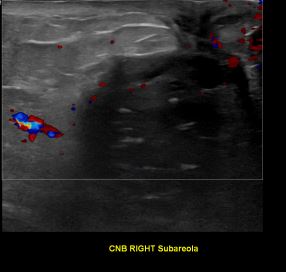

상기환자는 외부병원이상소견으로 조직검사 권유받고 내원하신 70대초반 여성분으로 의심스러운 우측혹 조직검사 시행해 유방암 진단되었습니다.